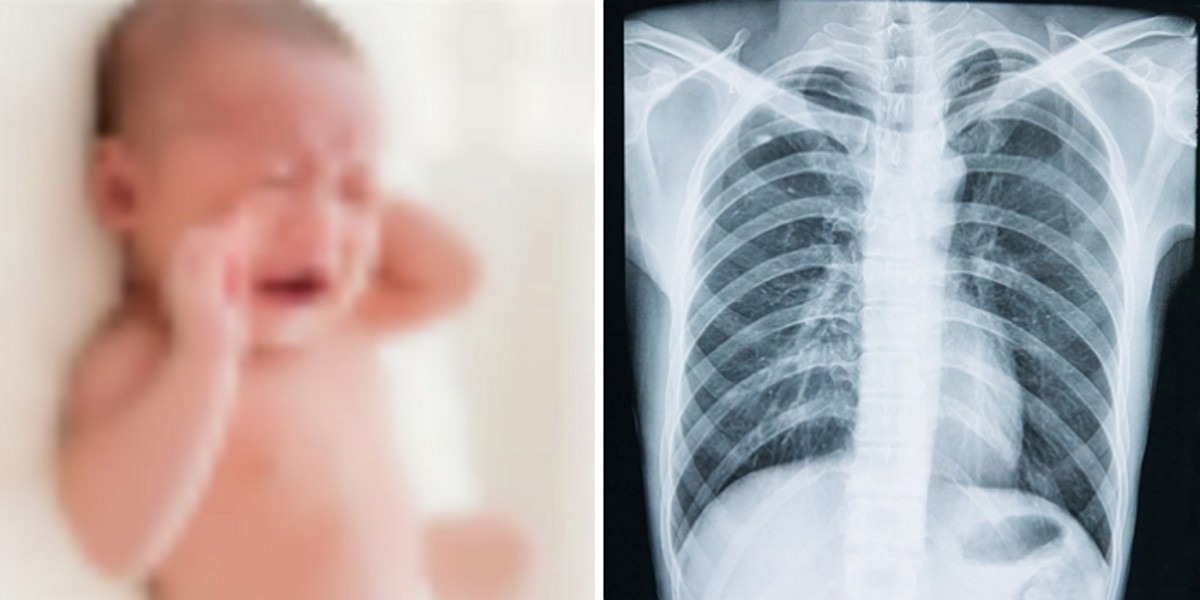

인사이트기사의 이해를 돕기 위한 자료 사진 / gettyimagesBank

A씨의 구체적인 학대 방법은 확인되지 않았으나, 사망한 C군의 늑골 29곳이 골절된 것으로 확인됐다.

또 피해 아동을 부검한 국립과학수사연구원 부검의는 "피해자의 골절은 오래된 학대로 인해 발생한 것으로 의심되며, 두부 손상은 누가 보더라도 '저 정도로 세게 흔들면 죽을 수 있겠다' 싶을 정도로 강하게 흔들어야만 발생할 수 있는 증상"이라는 의견을 낸 것으로 전해졌다.